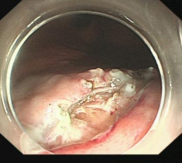

消化道早癌的病例展示(经内镜手术或活检证实):

胃窦的腺癌 行ESD治疗

术中见较粗穿支血管,裸化后凝除,最终高效、安全的切除病灶。